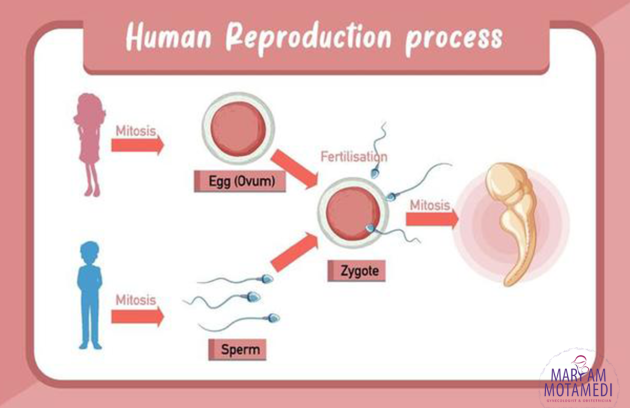

تاریخچه ی تولید مثل چیه؟